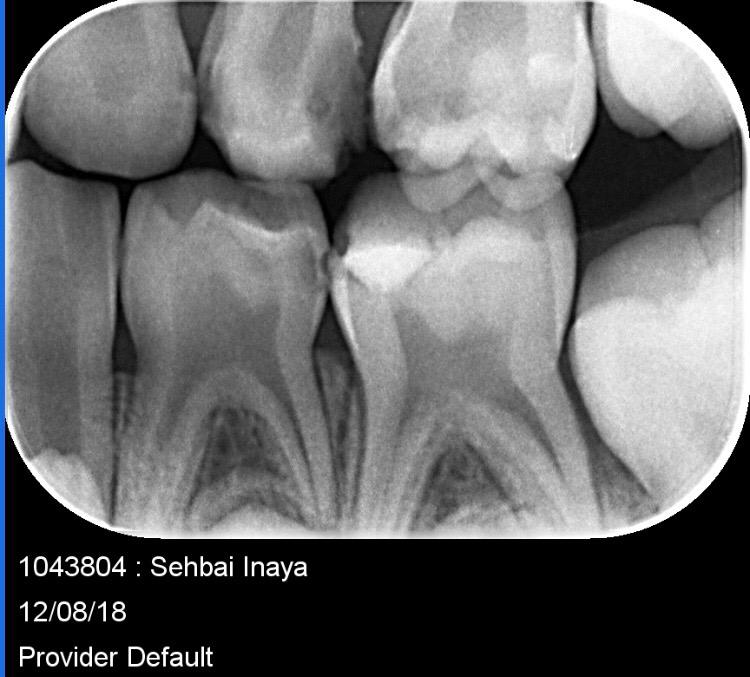

My daughter is 7 and hav deep cavity I took her to dentist one said she need 1 extraction and when I went to pediatric dentist she said she needs 4 extractions which she is going to do altogether same day I am attaching her xrays can any dentist plz advise after looking at the xrays thanks

Her both upper D are definitely for extraction and for her E need to evaluate clinically as well there might get b some Endodontic treatment and space maintainers afterwards

After extraction she will need space maintainer to keep first molar in its place so better to go for RCT to keep this tooth till age 12